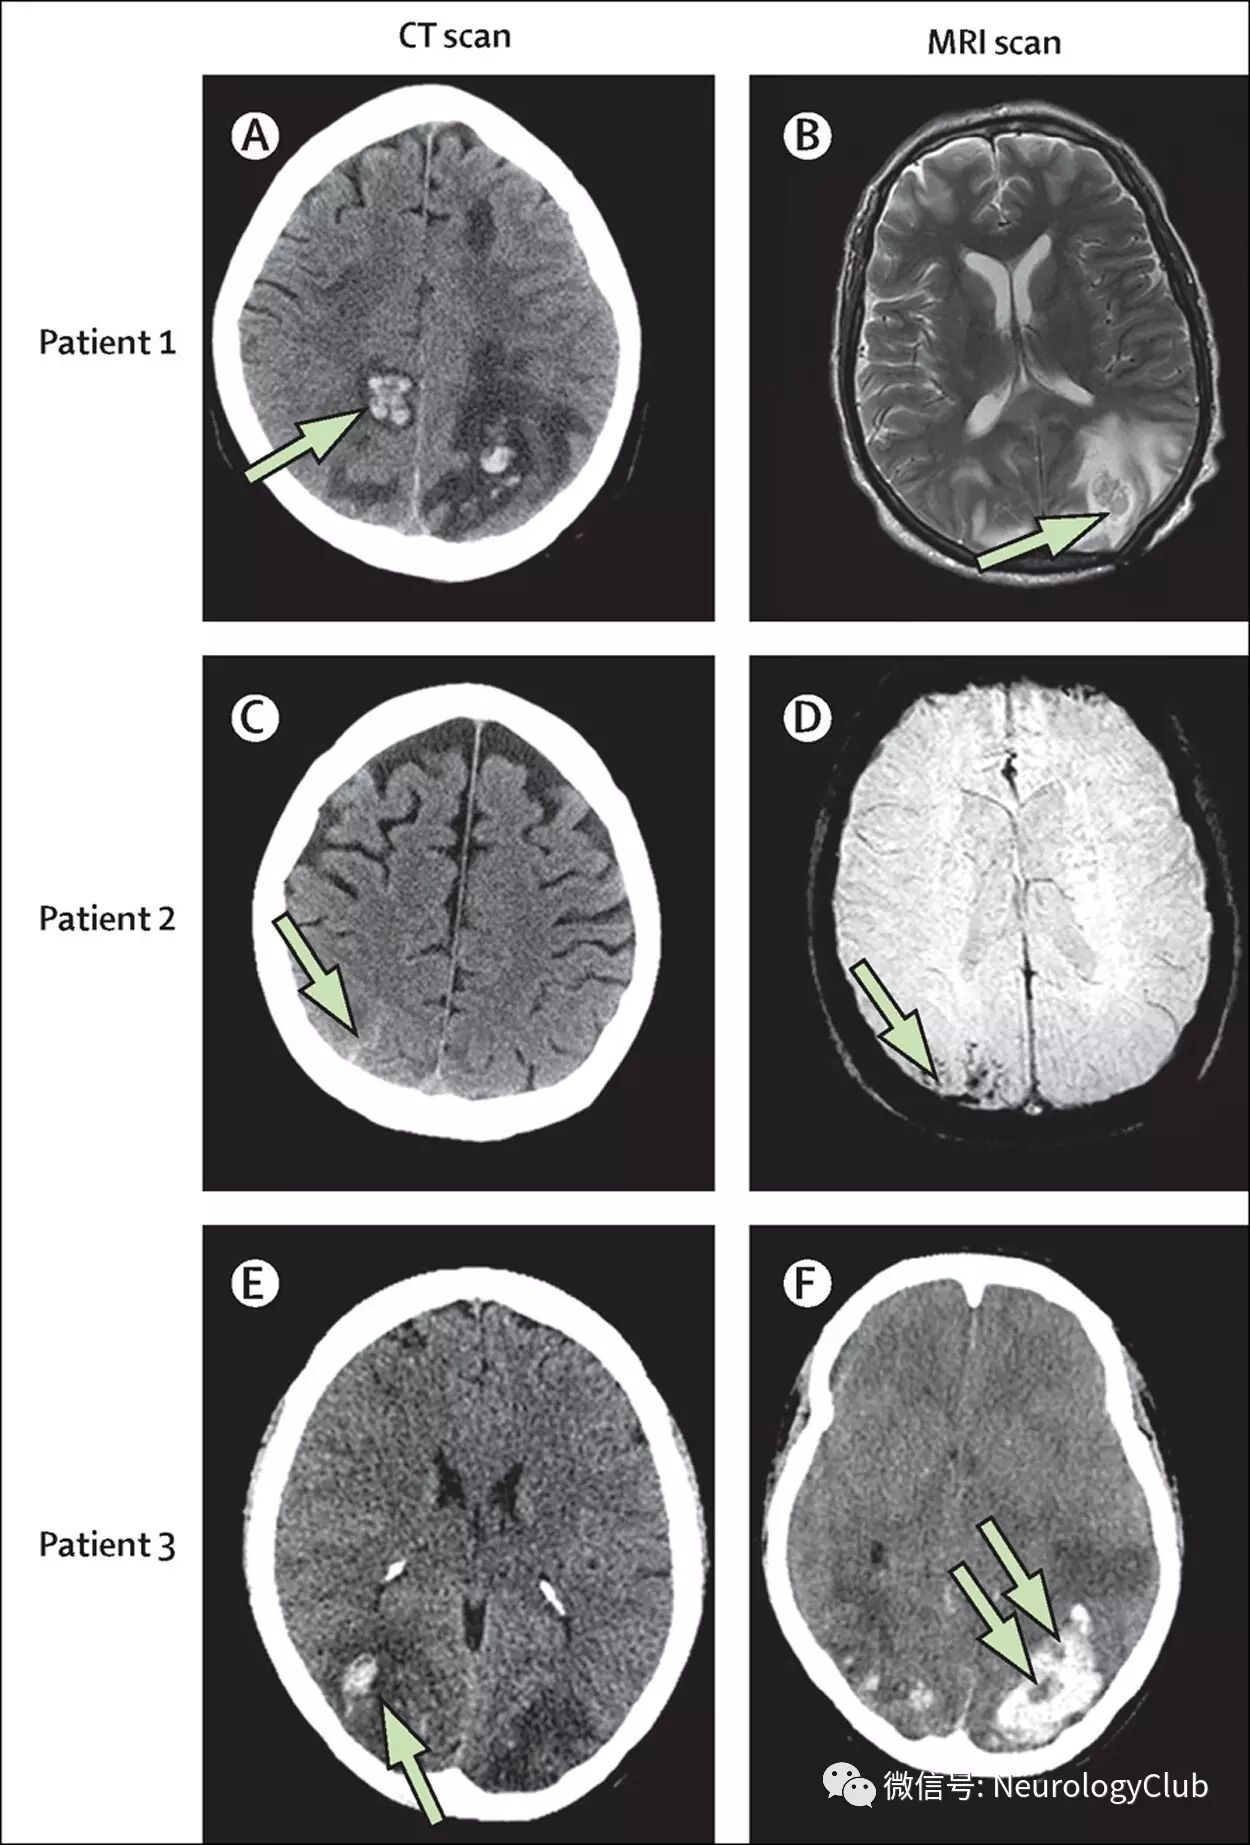

10-25%PRES患者可伴有颅内出血。脑实质出血最常见,而蛛网膜下腔出血次常见。出血患者中约18-30%同时存在两者类型出血。异基因骨髓移植后罹患PRES者颅内出血几率更大。一项应用SWI序列的研究显示58%18/31)患者可见微出血,但其临床意义不明确。

9:PRES伴脑出血

约15-30%患者在MRI上可见弥散受限。弥散受限部位通常是位于大片血管源性水肿部位的较小病灶。弥散受限病灶的出现通常与不可逆的损伤和临床不完全恢复相关。DWI高信号时,对应ADC值可低、等或高(见图5)。ADC值增加的区域根据T2透射效应(T2 shine-through effect)的数量在DWI上可表现为高、低或等信号。高ADC值病灶最可能是可逆的,而ADC值下降通常进展为真正的梗死。(注:T2透射效应即指DWI上的信号仍包含着T2弛豫时间的影响,因此DWI上的高信号病灶可能反应了强T2透射效应,而不是弥散减少。DWI低信号病灶是由于不能被T2效应平衡的更高ADC值所致)

(图5:PRES弥散受限表现)